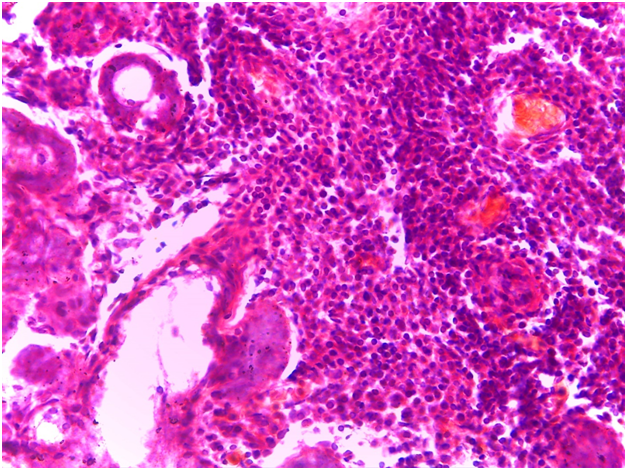

For Sjögren’s syndrome, salivary gland biopsy specimens have shown numerous lymphocytic foci in 4 mm2 (count > 50 lymphocytes per focus) within the glandular parenchyma. Acinar degeneration and few epimyoepithelial islands were detected. There was no substantial confluence of lymphocytes in a germinal-center-orientation within the submitted cases (Figure 3 & Figure 4). Focusing on characterizing any histopathological changes in GBS, the submitted cases of GBS revealed, in the asymptomatic glandular specimens, conspicuous perivascular and periductal infiltrations of neutrophils and macrophages. Moreover, vascularity was richer than that of normal mucosa whose vascular components were inconspicuous. Hemorrhagic spots, intervening extravasation of RBCs as well as dark acini, comparable to dust cells in smoking alveolitis, were also evident (Figure 5 & Figure 6).

Figure 3 Photomicrograph showing confluence of lymphocytic foci that infiltrate most of the architecture of the glandular parenchyma with acinar degeneration and epimyoepithelial proliferations. (H&E stained, Original magnification 10x).

Figure 4 A higher magnification of the previous photomicrograph in which a confluence of lymphocytes replaces the glandular parenchyma and degenerates the acini. (H&E stained, Original magnification 40x).